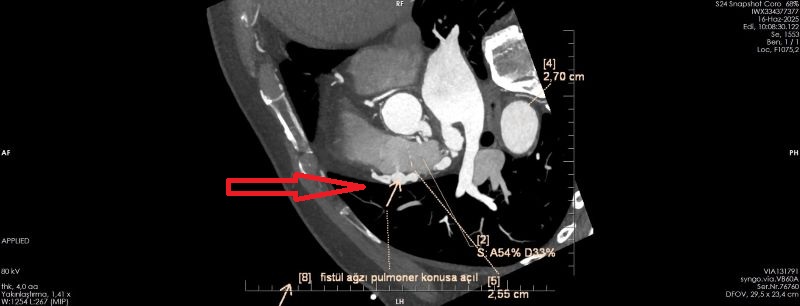

OLGU:

Koroner arterin pulmoner artere füstülizasyonu ile Koroner BT Anjiyografi ile demosterize edilmiş olgu örneğidir.